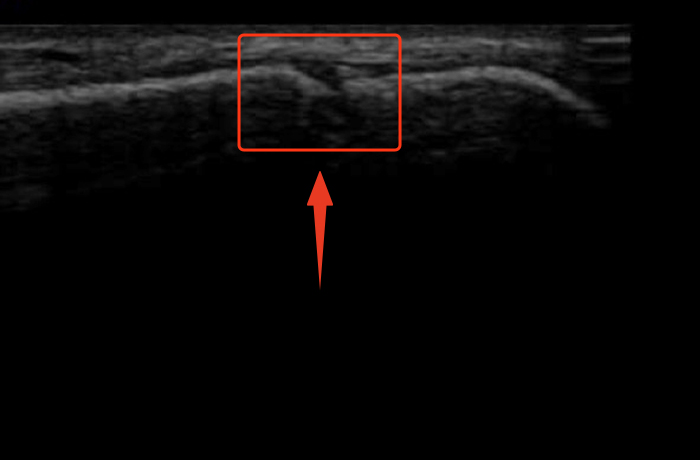

① まだまだ伸びる時期

この時期は、骨端線がはっきりと開いていて、軟骨部分が広い状態です。

活発に骨が成長しており、年に数㎝以上と大きく身長が伸びる傾向にあります。特に思春期に入る前や思春期の初期に多く見られます。